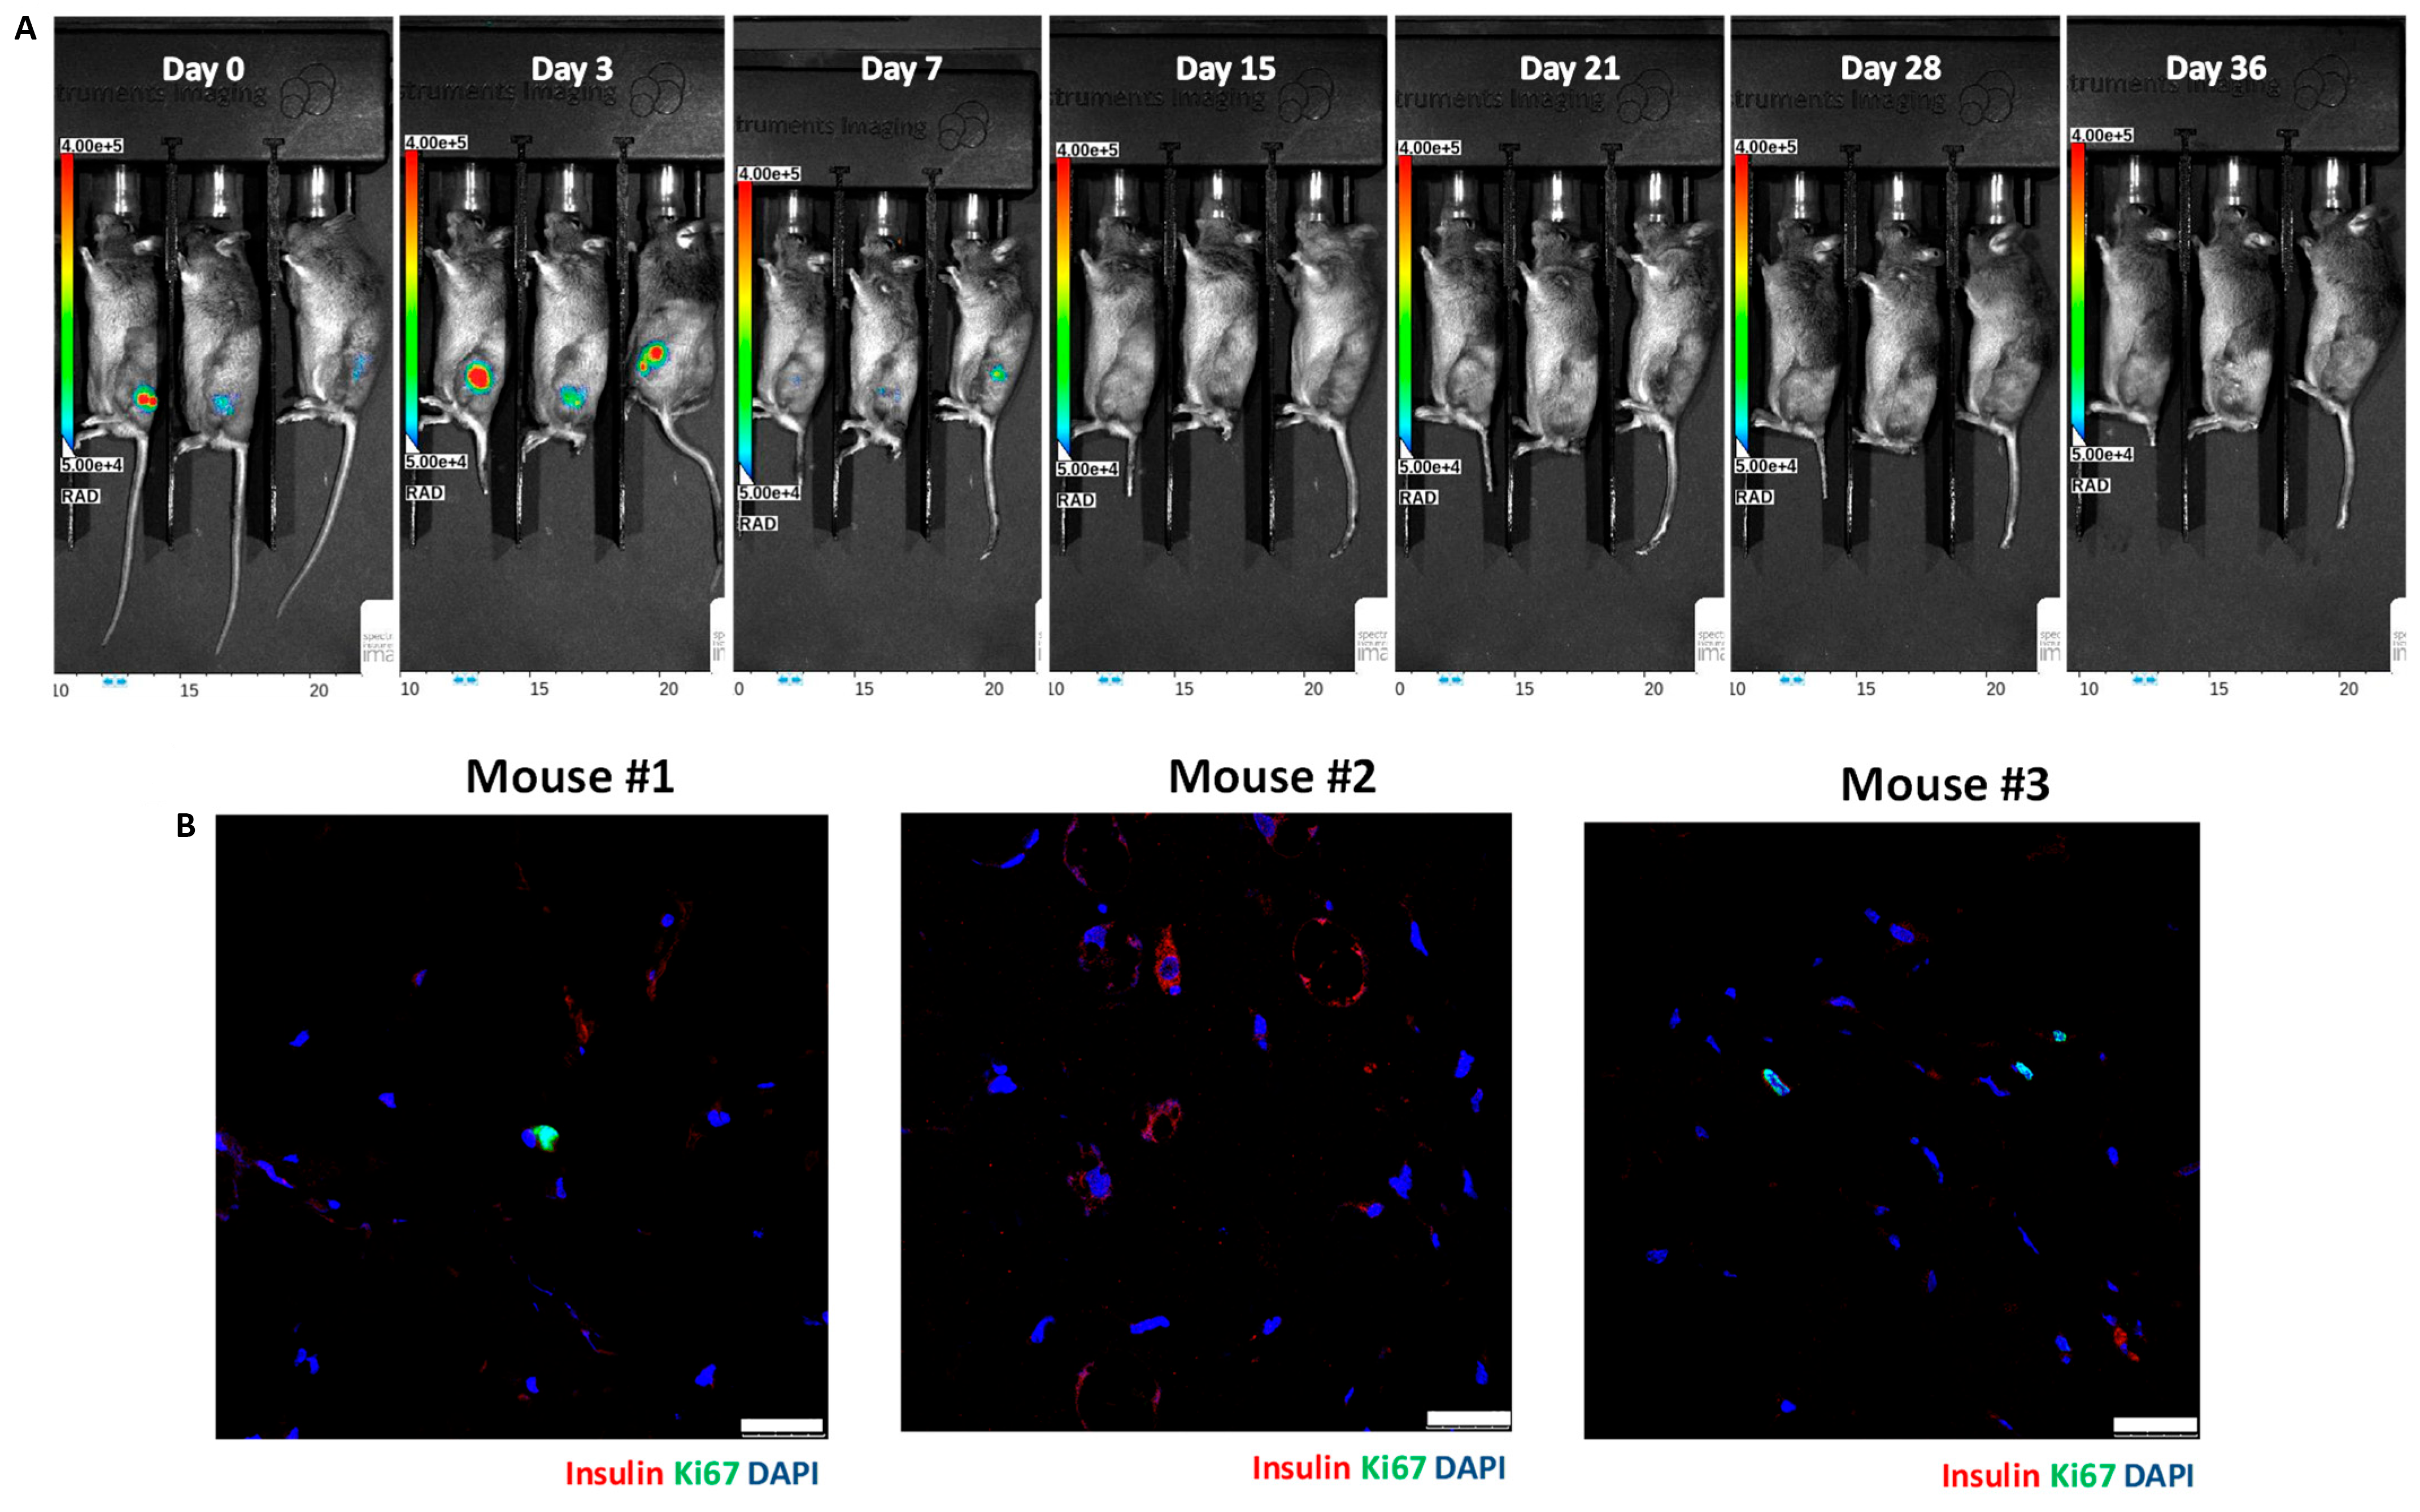

3.2. In Vivo Bioluminescence Imaging of Matrigel-Embedded MIN6 Cells Subcutaneously Transplanted in Nude and C3H Mice

3.3. Histology of Subcutaneous Matrigel-Embedded MIN6 Cell Grafts in Nude and C3H Mice